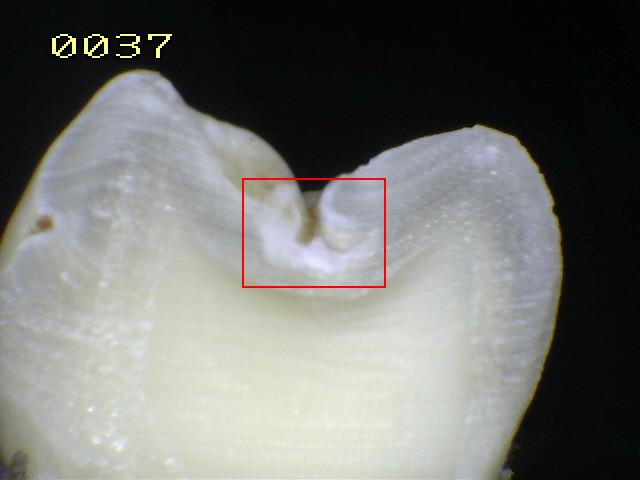

Espécimen Nº 14 |

Corte sagital |

Verificando un

código

1 histológico |